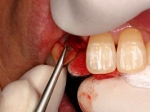

抜歯を行う。折れていた位置がかなり深い位置であるのがわかる。

歯根も抜歯